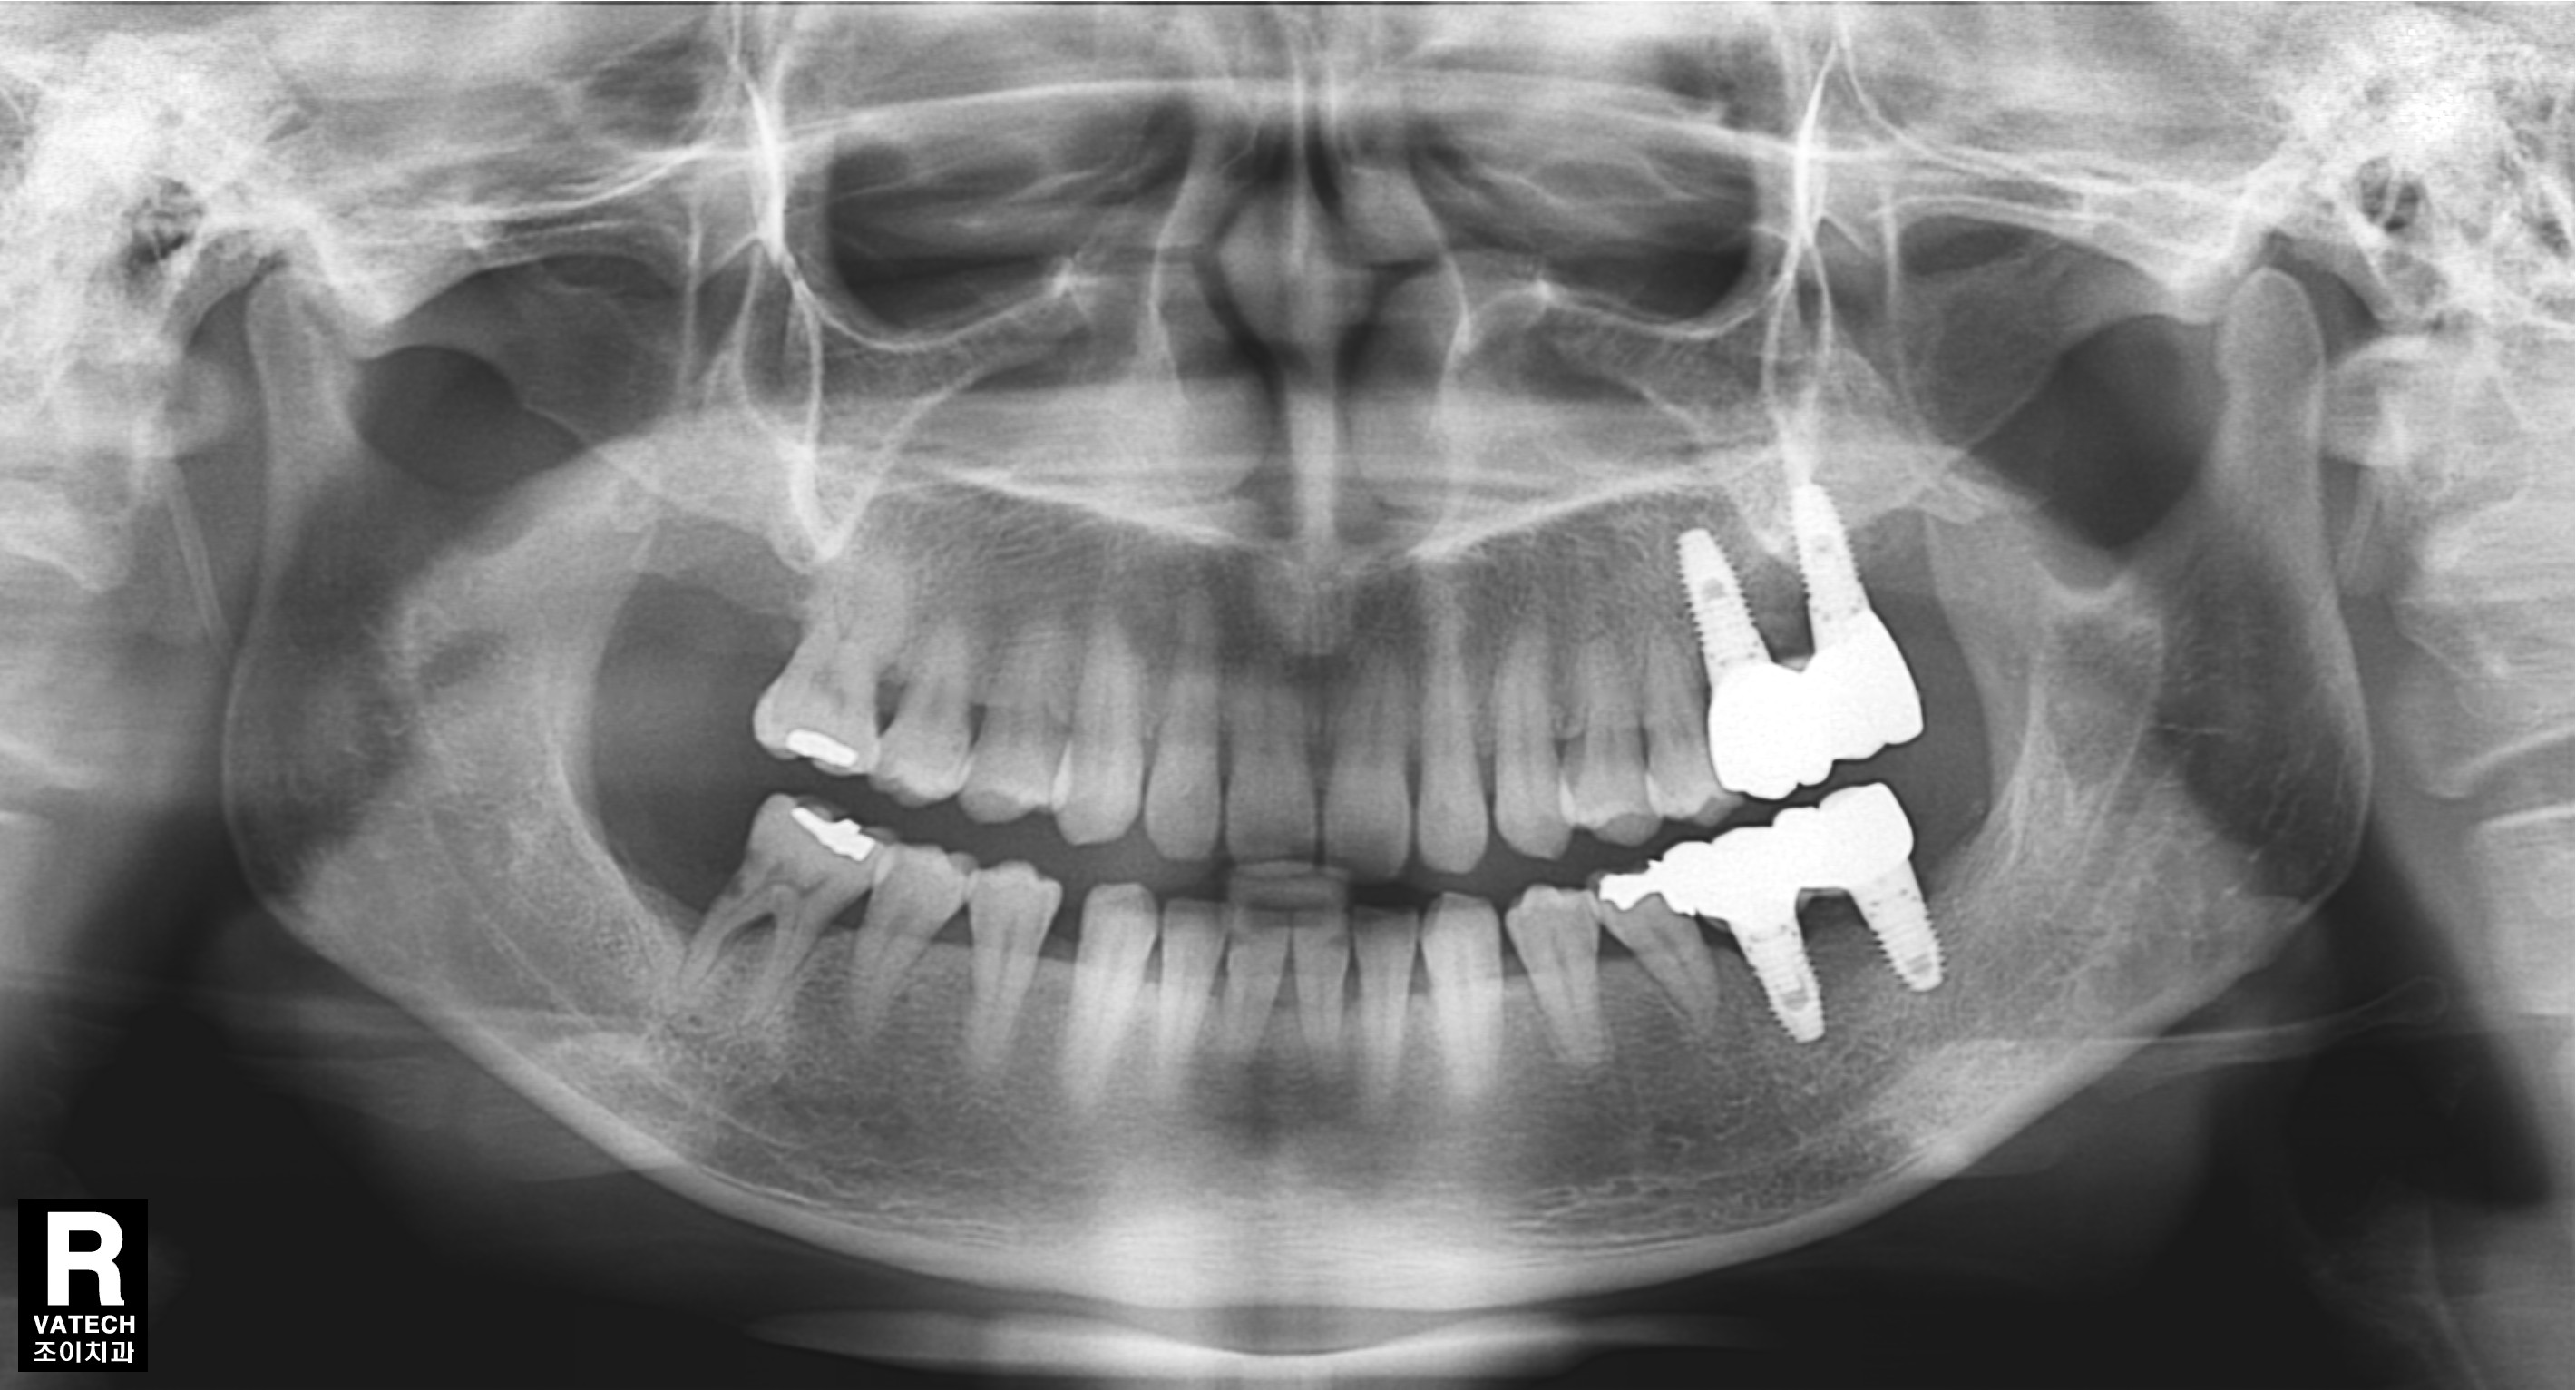

치주질환으로 치조골이 많이 녹아 내려간 경우 원하는 위치에 바로 임플란트를 심을 수 없는 경우가 많습니다.

또한 임플란트의 실패율도 높아집니다.

이 경우 골을 이식하는 것을 먼저 하고 수개월이 경과한 후에 다시 임플란트를 심어야 합니다.

그래야 원하는 위치에 임플란트를 심을 수 있고, 성공율을 높이며, 장기간 문제 없이 잘 유지할 수 있습니다.